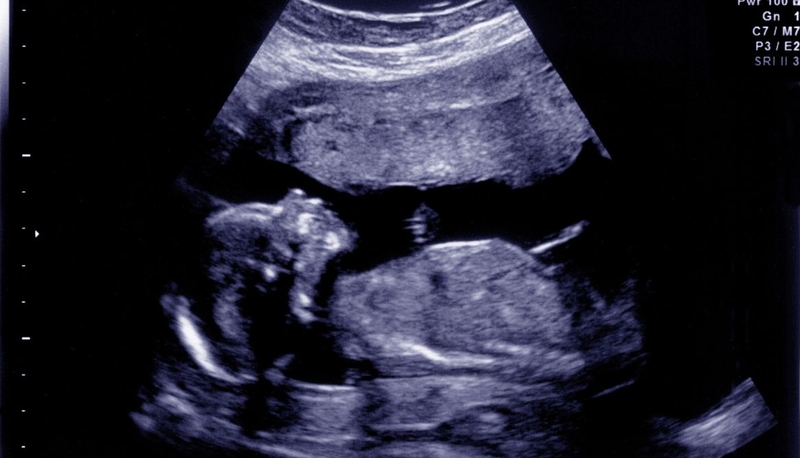

Bất sản xương mũi là dị tật bẩm sinh hiếm gặp, đặc trưng bởi tình trạng xương mũi của thai nhi không phát triển (bất sản toàn phần) hoặc phát triển không đầy đủ (bất sản một phần). Dị tật này thường được phát hiện qua siêu âm từ tuần thai thứ 11 - 14. Dị tật này có thể đơn độc hoặc đi kèm các bất thường khác như hở hàm ếch, dị tật tim. Nhóm đối tượng nguy cơ cao bao gồm thai phụ trên 35 tuổi, tiền sử gia đình có dị tật di truyền, hoặc kết quả sàng lọc trước sinh bất thường.

Dấu hiệu nhận biết bất sản xương mũi ở trẻ sơ sinh chủ yếu thể hiện qua đặc điểm hình thái mũi và các bất thường đi kèm. Về hình thái, trẻ có thể có sống mũi phẳng, mũi ngắn hoặc gần như không thấy sống mũi, khiến khuôn mặt trở nên thiếu điểm nhấn ở vùng trung tâm. Một số trường hợp, mũi trẻ có hình dạng bất thường rõ rệt, dễ nhận biết ngay sau sinh. Cũng có thể qua siêu âm thai kỳ từ tuần 11 - 14 thấy xương mũi không quan sát được ở mặt cắt dọc giữa trên hình ảnh siêu âm.